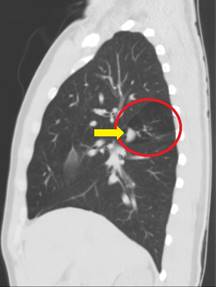

Los hallazgos de la TAC de tórax (Figuras 6-8) correspondieron a la presencia de imagen nodular irregular parahiliar derecha con hiperinflación segmentaria distal a la alteración. Se realizó fibrobroncoscopia para exploración de la vía aérea, la cual fue normal. Se dio egreso de la consulta de Neumología sin indicación quirúrgica debido a la ausencia de síntomas e infección respiratoria recurrente.

Figura 6: Tomografía de tórax-plano coronal. El círculo rojo enmarca una región hipodensa en el lóbulo superior derecho. La flecha evidencia el mucocele del bronquio atrésico.

Figura 7: Tomografía de tórax-plano sagital derecho. El círculo rojo enmarca una región hipodensa en el lóbulo superior derecho. La flecha evidencia el mucocele del bronquio atrésico.